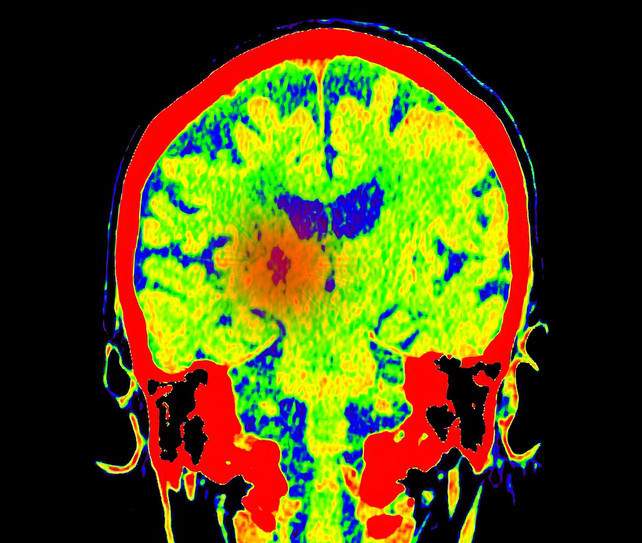

Baş ağrısı ve unutkanlığı hafife almayın! Altından bir tümör çıkabilir

Dünya Sıhhat Örgütü datalarına nazaran 130’dan fazla çeşidi bulunan beyin tümörlerinde artık ‘hastalık’ değil, ‘hasta’ tedavi ediliyor.

Günümüzde patoloji, yalnızca mikroskop altında hücre incelemesi yapmanın ötesine geçerek tümörün genetik haritasını çıkarıyor. Yeni jenerasyon dizileme (NGS) üzere moleküler formüllerle tümörün DNA’sındaki değişiklikler tahlil edilerek; hastalığın seyri öngörülüyor ve direkt tümör hücresini maksat alan akıllı ilaçlar seçiliyor.